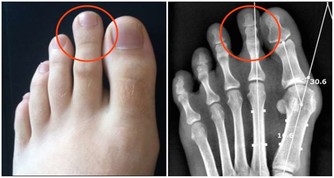

如果你的腳趾頭又瘦又短,腳部整體輪廓也是細又長,那你的身體好像不是很好喔!

因為小腳趾是足少腎經的源頭,所以小腳趾較粗較厚實的多是腎氣足的,而相反就是腎氣虧的。

腳趾甲觀察你的腳趾甲,有沒有白色的半月牙,

如果每個腳趾甲都是粉嫩的顏色,趾甲底部有1/5的月牙,就是很健康的腳趾甲。

趾甲顏色發白:很可能是貧血、營養不良,需要增加營養。

趾甲上面有縱行的紋路:那就說明你的身體極度疲憊,機能及抵抗力已經降低,要注意休息。

大拇趾趾甲往上翹起:你最近有很嚴重的視疲勞,或是本身有散光、近視。

5個腳趾甲的趾甲都有向上翹起的狀態:說明你最近壓力山大,需要及時排解壓力。